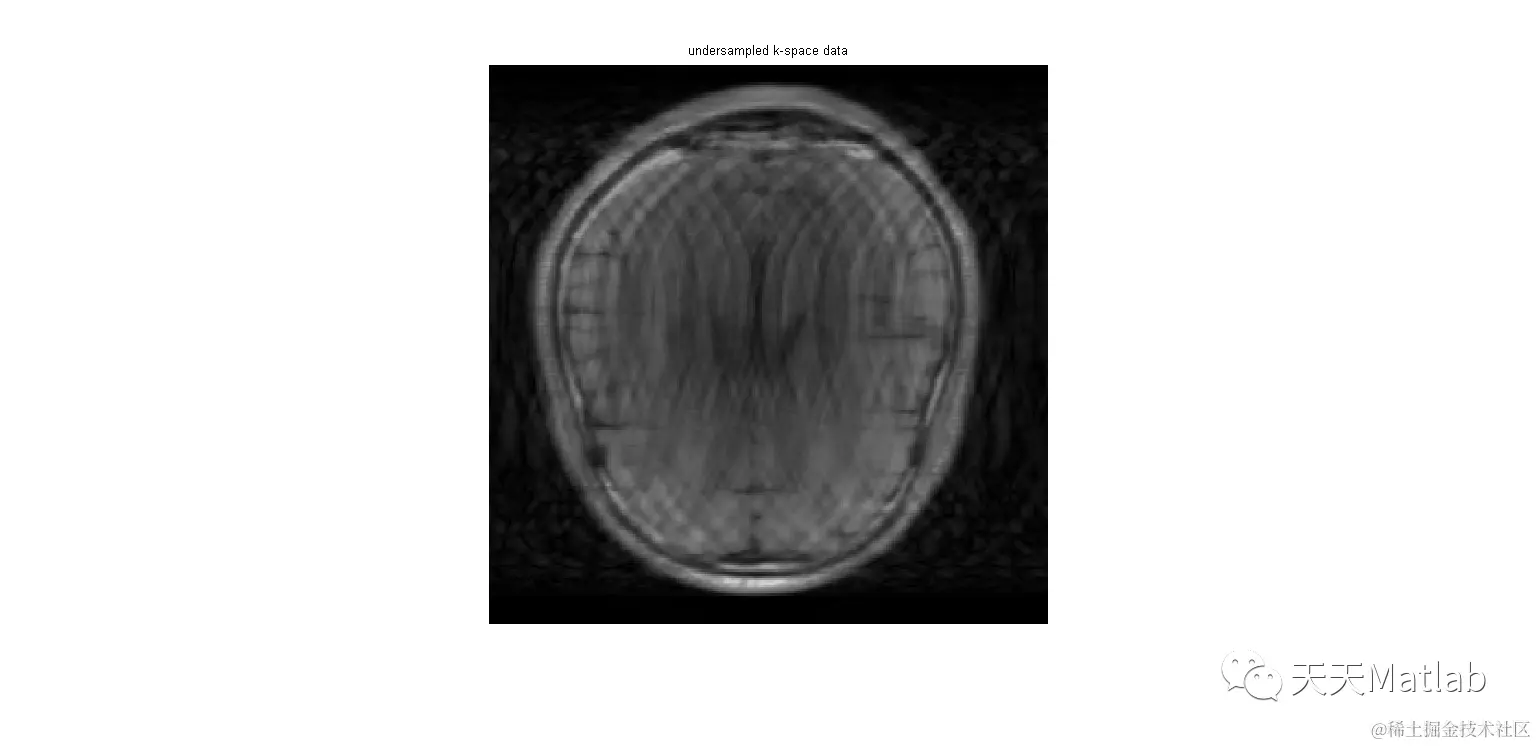

figure,imshow(abs(ifft2c(paramSIDWT.U'*y1))); title('undersampled k-space data')